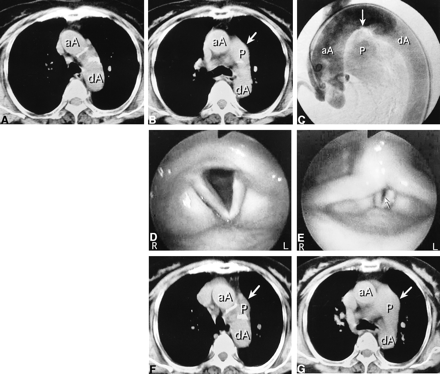

76-year-old woman with long-standing PDA.

A and B, Axial CT studies at age 74, obtained for dyspnea, before left vocal cord paralysis developed. The pulmonary trunk is not present at the level of the lower border of the aortic arch (A). At the level of the carina (B), the main pulmonary trunk (arrow) is larger than normal.

C, Digital subtraction aortogram, lateral view, at age 75, shows flow into the pulmonary artery through the PDA (arrow).

D and E, At age 76, endoscopic views of larynx during quiet respiration (D) and phonation (E) show a large glottic gap (arrow) due to bowing of the paralyzed left vocal cord.

F and G, Axial CT scans at age 76, obtained after paralysis developed. At the level of the lower border of the aortic arch (F), the pulmonary trunk (arrow) is present in the same section in which it was not seen before (A). There are no other mediastinal lesions. At the level of the carina (G), an enlarged and upwardly displaced pulmonary trunk (arrow) is seen adjacent to the expected course of the left recurrent laryngeal nerve.

aA indicates ascending aorta; dA, descending aorta; P, pulmonary trunk.